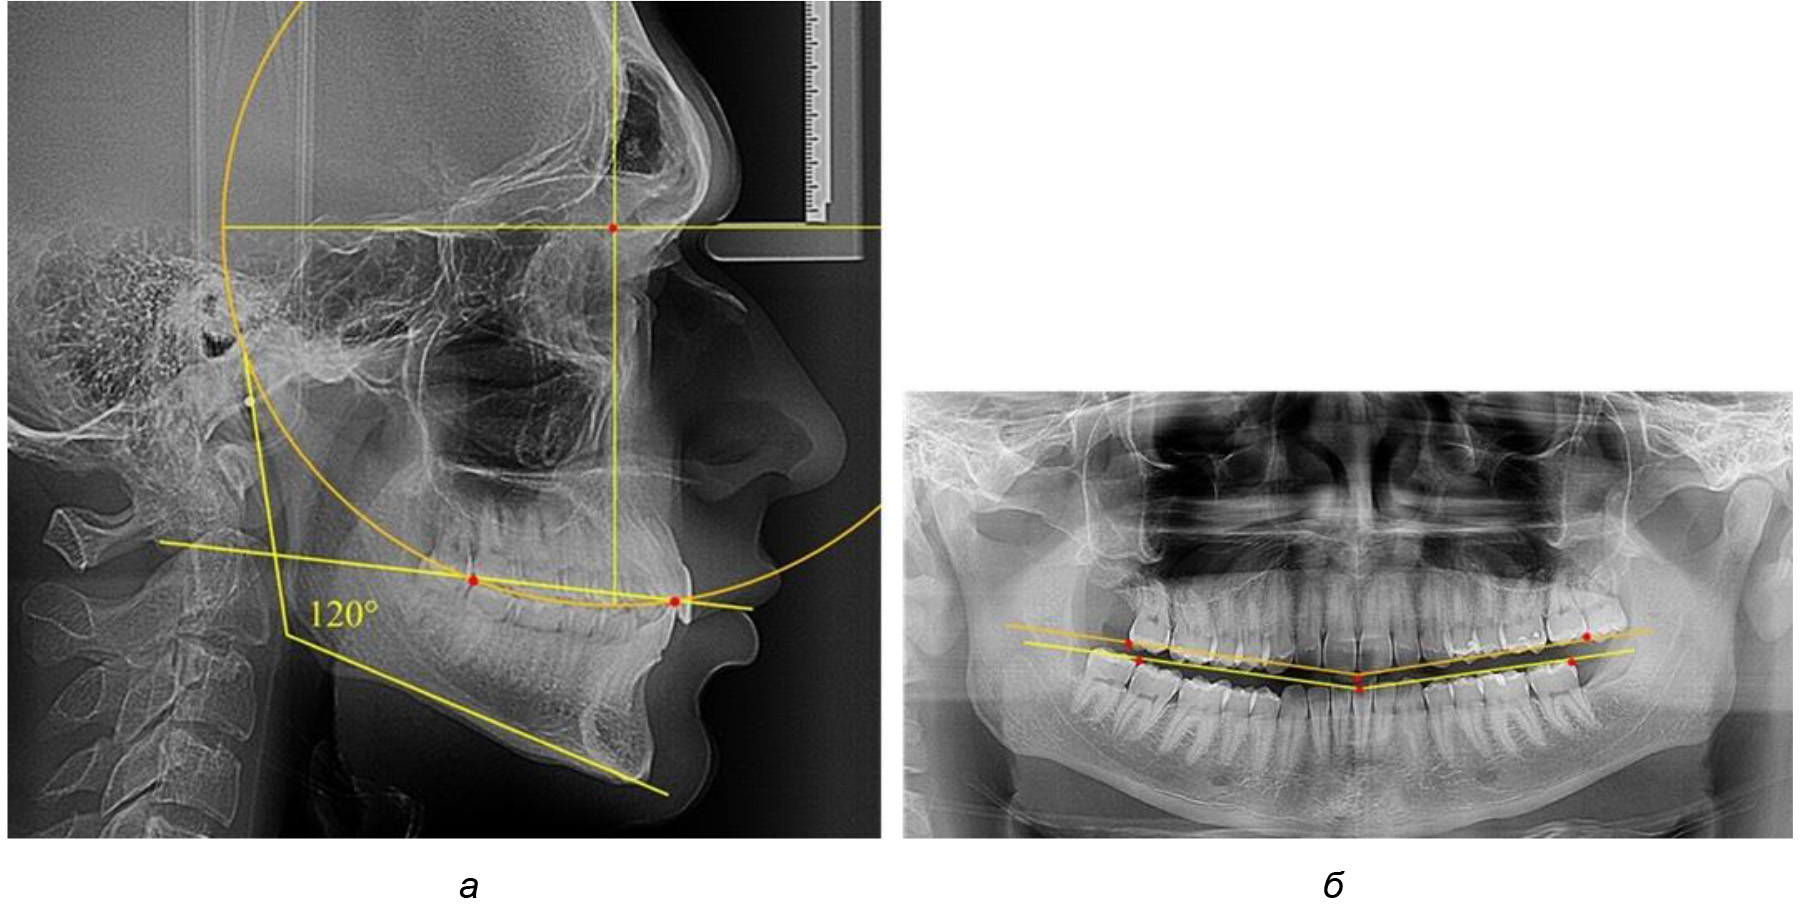

В 3-ю подгруппу вошли ТРГ и ОПТГ 14 человек 1-й группы, что составило (22,58 ± 5,31) % от общего количества людей 1-й группы. Величина угла нижней челюсти в среднем составила (114,85 ± 2,87)° и характеризовала горизонтальный тип нижней челюсти.

Глубина кривой Spee в среднем по 2-й подгруппе составил (2,94 ± 0,47) мм, что было меньше, чем в других подгруппах. Деление величины радиуса круга к длине окклюзионной линии составило 1,616 ± 0,02 (рис. 4).

Рис. 3. Особенности кривой Spee на ТРГ (а) и ОПТГ (б) при нейтральном типе роста нижней челюсти

Рис. 4. Особенности кривой Spee на ТРГ (а) и ОПТГ (б) у людей с горизонтальным типом лица